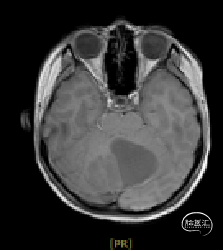

术后MRI

枕下后正中开颅小脑肿瘤切除术

术后病理